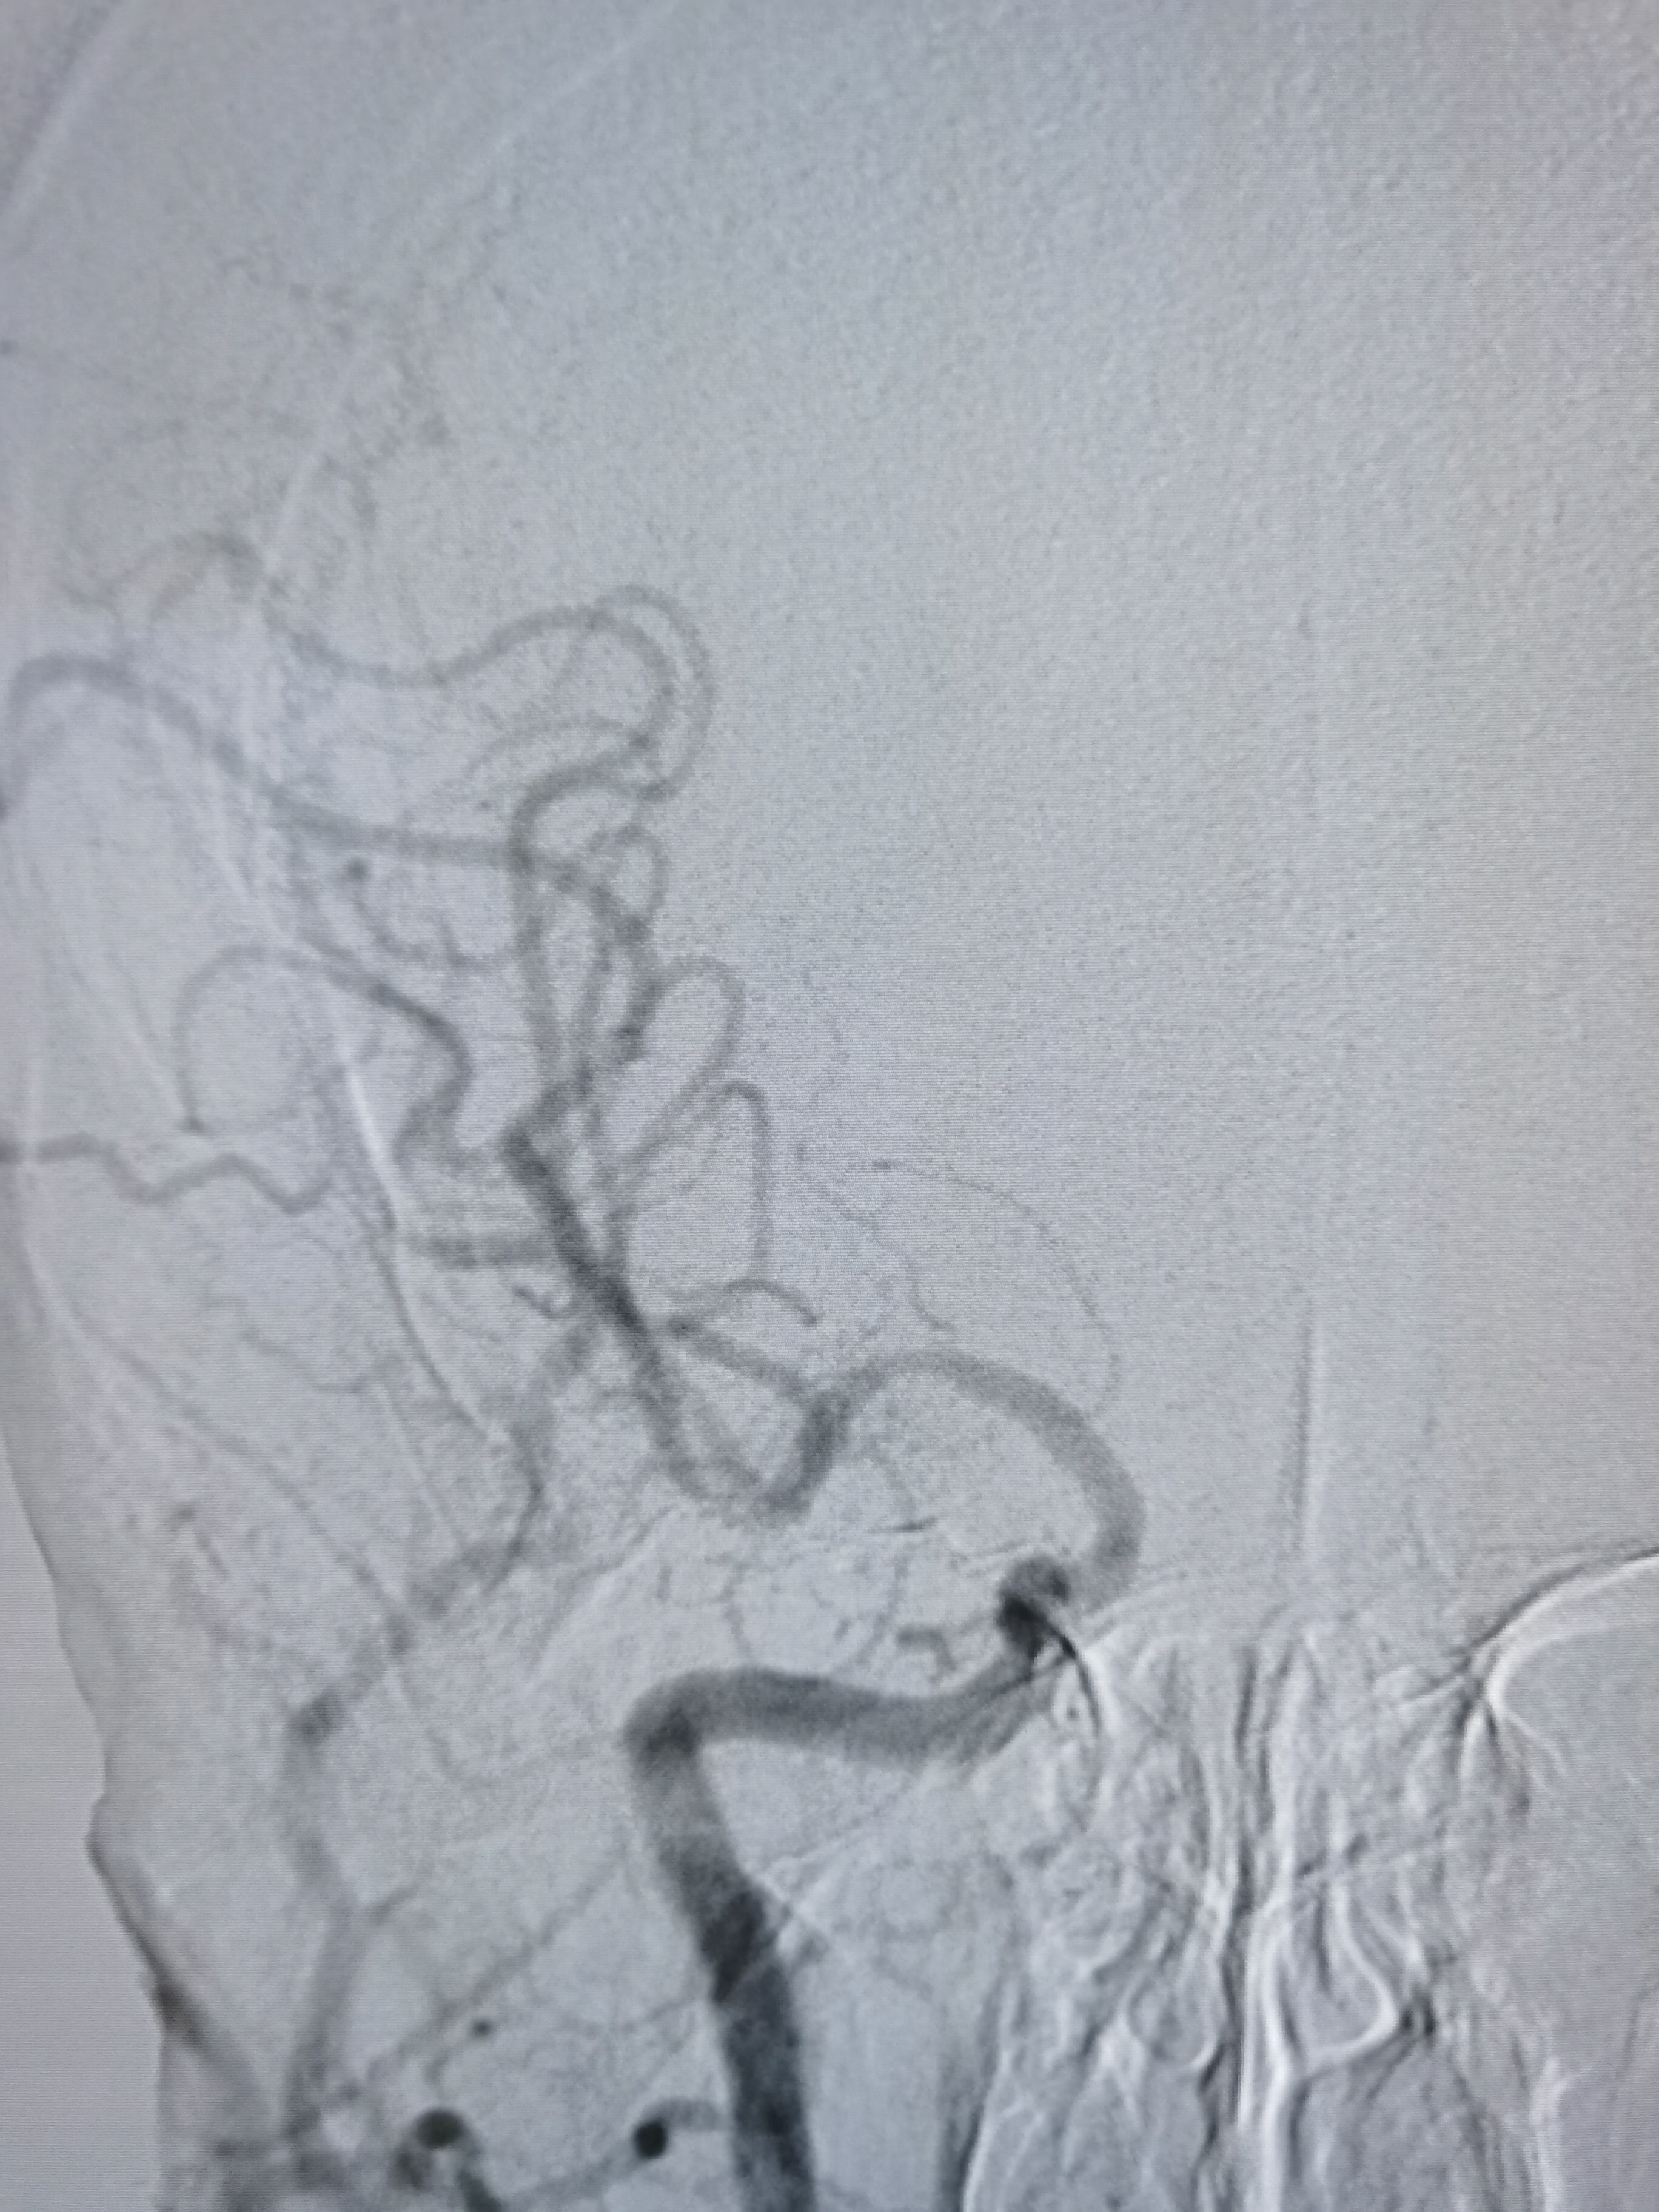

右侧颈内动脉起始部重度狭窄。

颅内段显影可。

右侧孤立大脑中动脉,M1轻度狭窄。